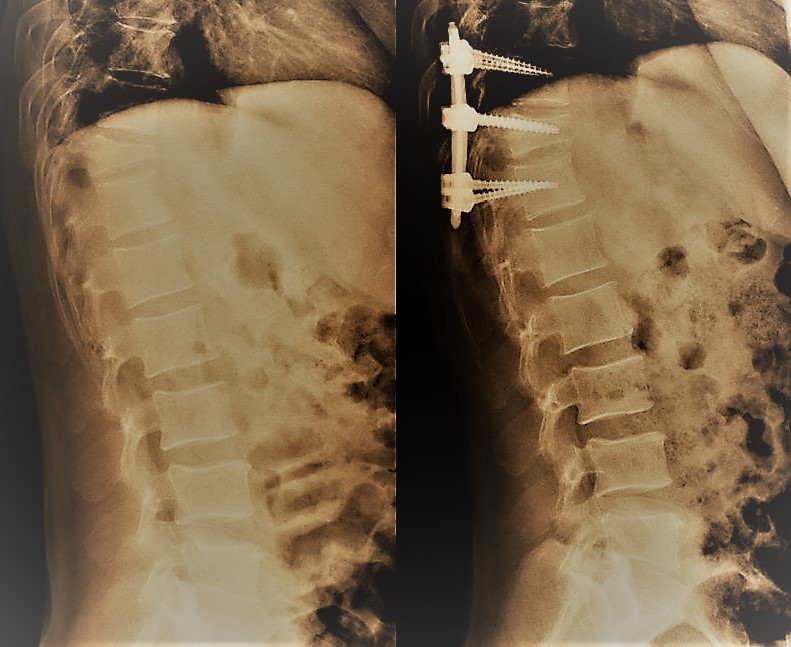

El tratamiento de las fracturas depende fundamentalmente del grado de deformidad asociado, la afectación de ligamentos (ambos aspectos definen la presencia o no de inestabilidad) y el que exista o no una lesión neurológica. En caso de fracturas estables sin déficit neurológico se emplea una ortesis mientras que en presencia de inestabilidad o afectación neurológica debe valorarse la cirugía.